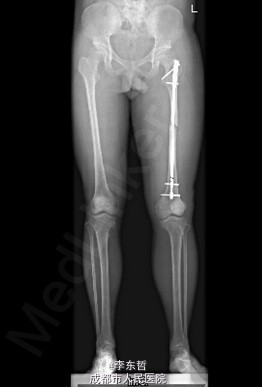

患者男,19岁,因“车祸伤致左下肢活动障碍5小时”入院。5小时前,患者骑电瓶车不慎与另一电动摩托车相撞倒地,当即感左大腿疼痛,畸形,活动受限,右小腿皮肤挫伤、出血,无头晕头痛,无大小便失禁。就诊于当地医院,检查提示:左股骨中段横行骨折。急诊行左大腿夹板外固定,右小腿清创缝合术,术后未进一步治疗,患者为进一步诊治来我院,急诊以左股骨中段骨折收入我科。 自患病以来,患者一般情况尚可,精神睡眠可,小便正常,大便未解。

查体:左大腿夹板固定,肿胀明显,短缩、畸形,右小腿内前方可见一长约5cm创口,已缝合,内植引流条一根,无明显肿胀。左大腿中段环周压痛,可扪及骨折断端,右小腿无明显压痛,双下肢感觉正常。左膝及髋关节明显活动受限,左足背及右下肢活动正常。 辅查:外院X片示:左侧股骨中上段可见骨质断裂征象,断端分离、错位、重叠,周围软组织肿胀;双侧胫腓骨、左膝关节各骨及左踝关节未见确切骨质断裂征象。

初步诊断:1、左股骨中段横行骨折,2、右小腿皮肤软组织裂伤清创缝合术后。 诊疗计划:1、向患者及家属交待病情及注意事项。2、向上级医生汇报患者病情。3、完善术前相关检查。4、给予皮肤牵引、抬高患肢等对症处理。5、拟进一步手术治疗。6、密切观察病情变化,根据病情及时处理